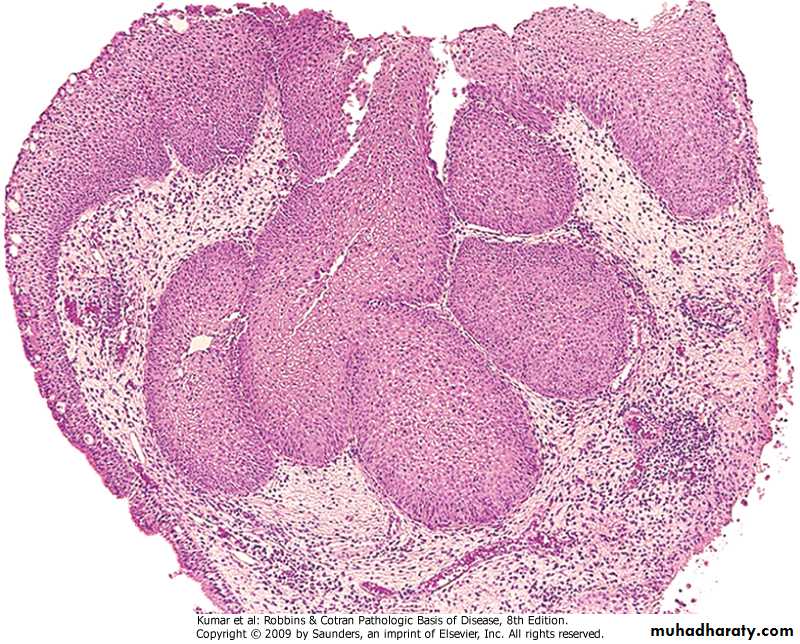

Bronchopneumonia

Patchy consolidation centered around inflamed bronchi & bronchiole. Multifocal & may be bilateral.

Pathology of Bronchopneumonia

Gross: Lesions are multiple & may be bilateral, affect basal segments of lower lobes.

Micro: Acute inflammation of bronchi ,extend to involve surrounding alveoli which become consolidated. May involve the pleura

Clinically: Fever cough sputum dyspnea